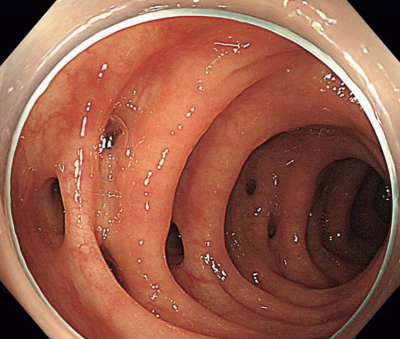

尿所見:蛋白(-)、糖(-)、潜血(-)。血液所見:赤血球 468 万、Hb 13.9 g/dL、Ht 42 %、白血球 12,300(桿状核好中球 30 %、 分葉核好中球45 %)、血小板 20 万。血液生化学所見:総蛋白 7.5 g/dL、アルブミン 3.9 g/dL、総ビリルビン 0.9 mg/dL、AST 28 U/L、ALT 16 U/L、LD 177 U/L(基準 120~245)、ALP 83 U/L(基準 38~113)、γ-GT 48 U/L(基準 8 ~50)、アミラーゼ 95 U/L(基準 37~160)、尿素窒素 12 mg/dL、クレアチニン 0.6 mg/dL、血糖98 mg/dL。CRP 3.2 mg/dL。 1 年前に行われた下部消化管内視鏡検査の S 状結腸像と今回来院時の腹部造影 CTを別に示す。